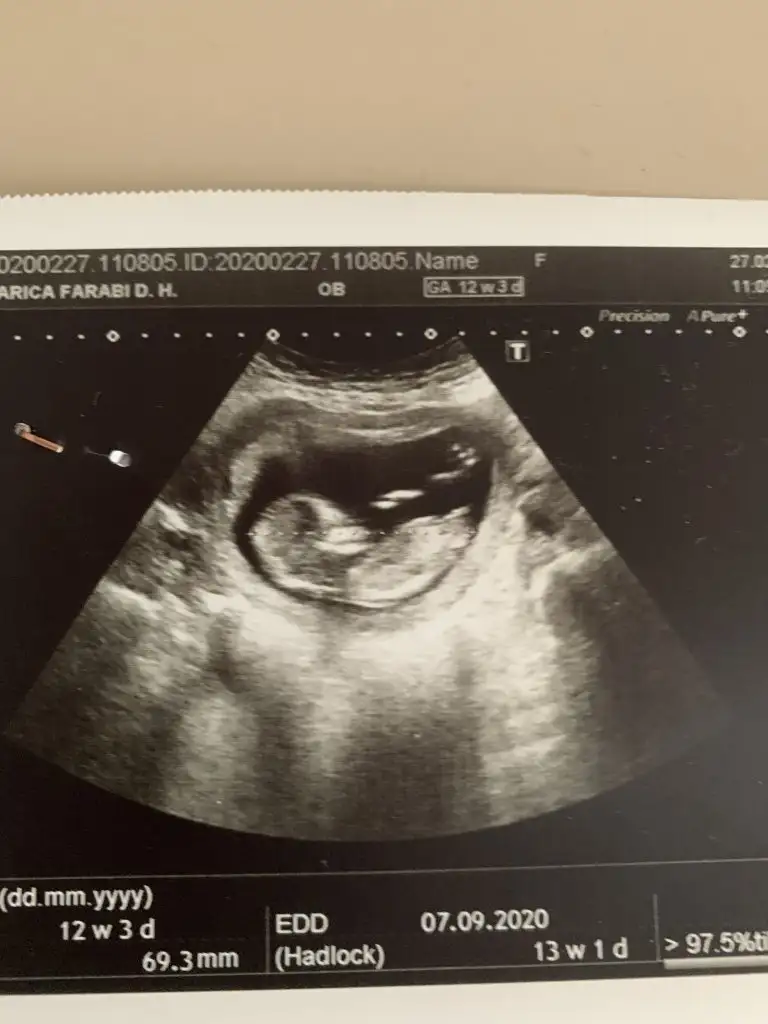

Ikra meyra Ikra meyra Bizede bakar mısınız? Daha öncede göndermiştim başka istemiştiniz. İki kızım var inşallah erkektir hayırlısı😊

iyi akşamlar kızlar bizede bir tahmin Varmı 12+6 haftalığız burada